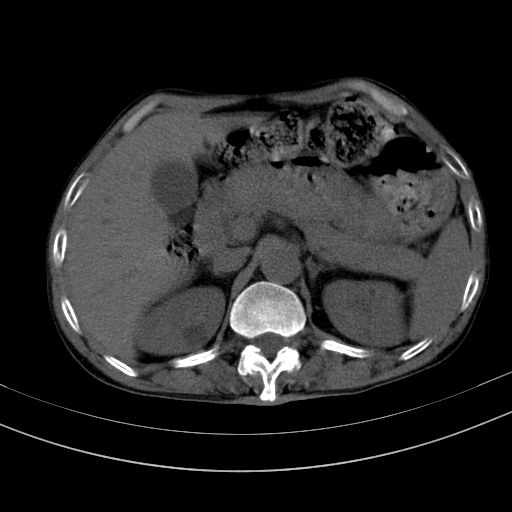

以下是引用dyqct在2010-1-9 17:56:00的发言:[br]考虑:1.双肾囊肿,左肾积水结石、旋转不良。[br] 2.右侧腹直肌血肿或纤维瘤。[br]肠道准备不好。做个增强。